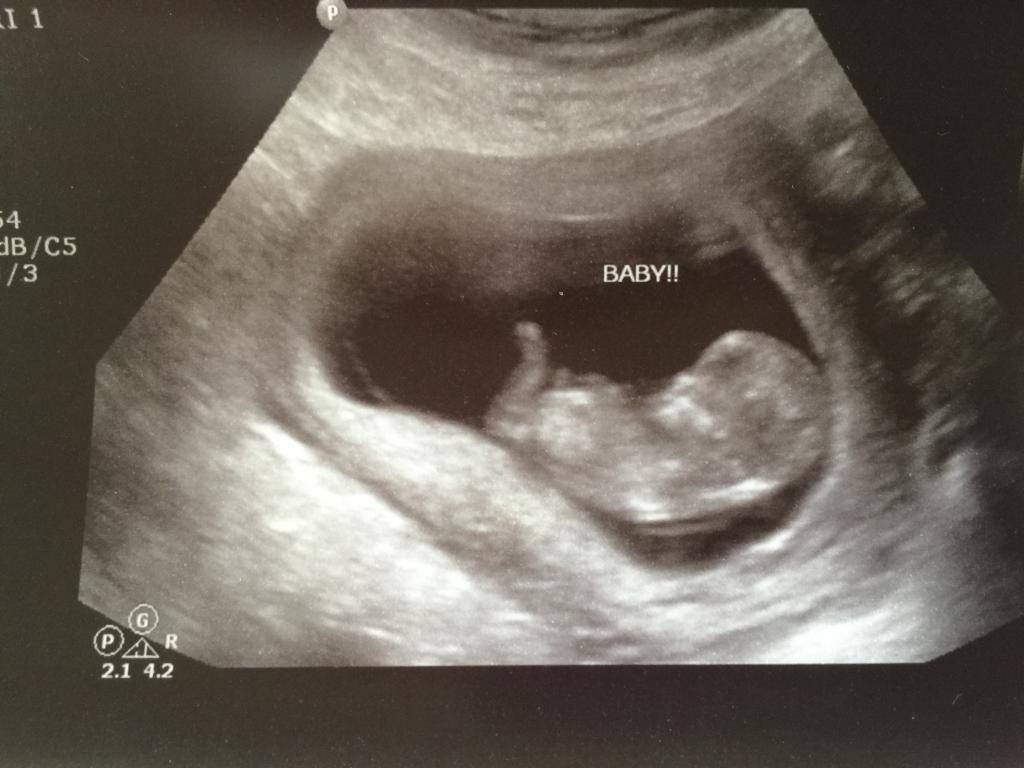

В календаре содержится вся необходимая информация по поводу плановых осмотров у врача. Женщина будет точно знать, когда следующий скрининг, какие анализы нужно сдать и на каком сроке, когда пойти на плановое УЗИ.

10 неделя — 5-сантиметровый эмбрион уже считается плодом, на УЗИ можно рассмотреть его пол. Его нервная система разделилась на центральную и периферическую, полушария мозга становятся более самостоятельными. Увеличенная матка нащупывается даже руками, постоянно хочется в туалет;

При использовании календаря беременности по неделям рассчитать пол возможно с вероятностью 50 х 50. Для того чтобы подтвердить или опровергнуть данные, лучше уточнить у специалиста во время УЗИ, показывает ли малыш свой пол. Правда, сделать это можно будет не раньше второго скрининга, который приходится на 17-19-ю неделю беременности. Случается, что на мониторе ничего не разобрать, или малыш отворачивается и прячет половые органы ножками. Судя по отзывам, так поступают девочки, мальчики же чаще всего показываются родителям во всей красе.

28 неделя — малышу ровно 7 мес., можно определить, будет ли он правшой или левшой. Для этого на УЗИ видно, какой ручкой он чаще тянется ко рту. Сурфактанта в легких уже достаточно для того, чтобы при первом вдохе не слипались альвеолы;